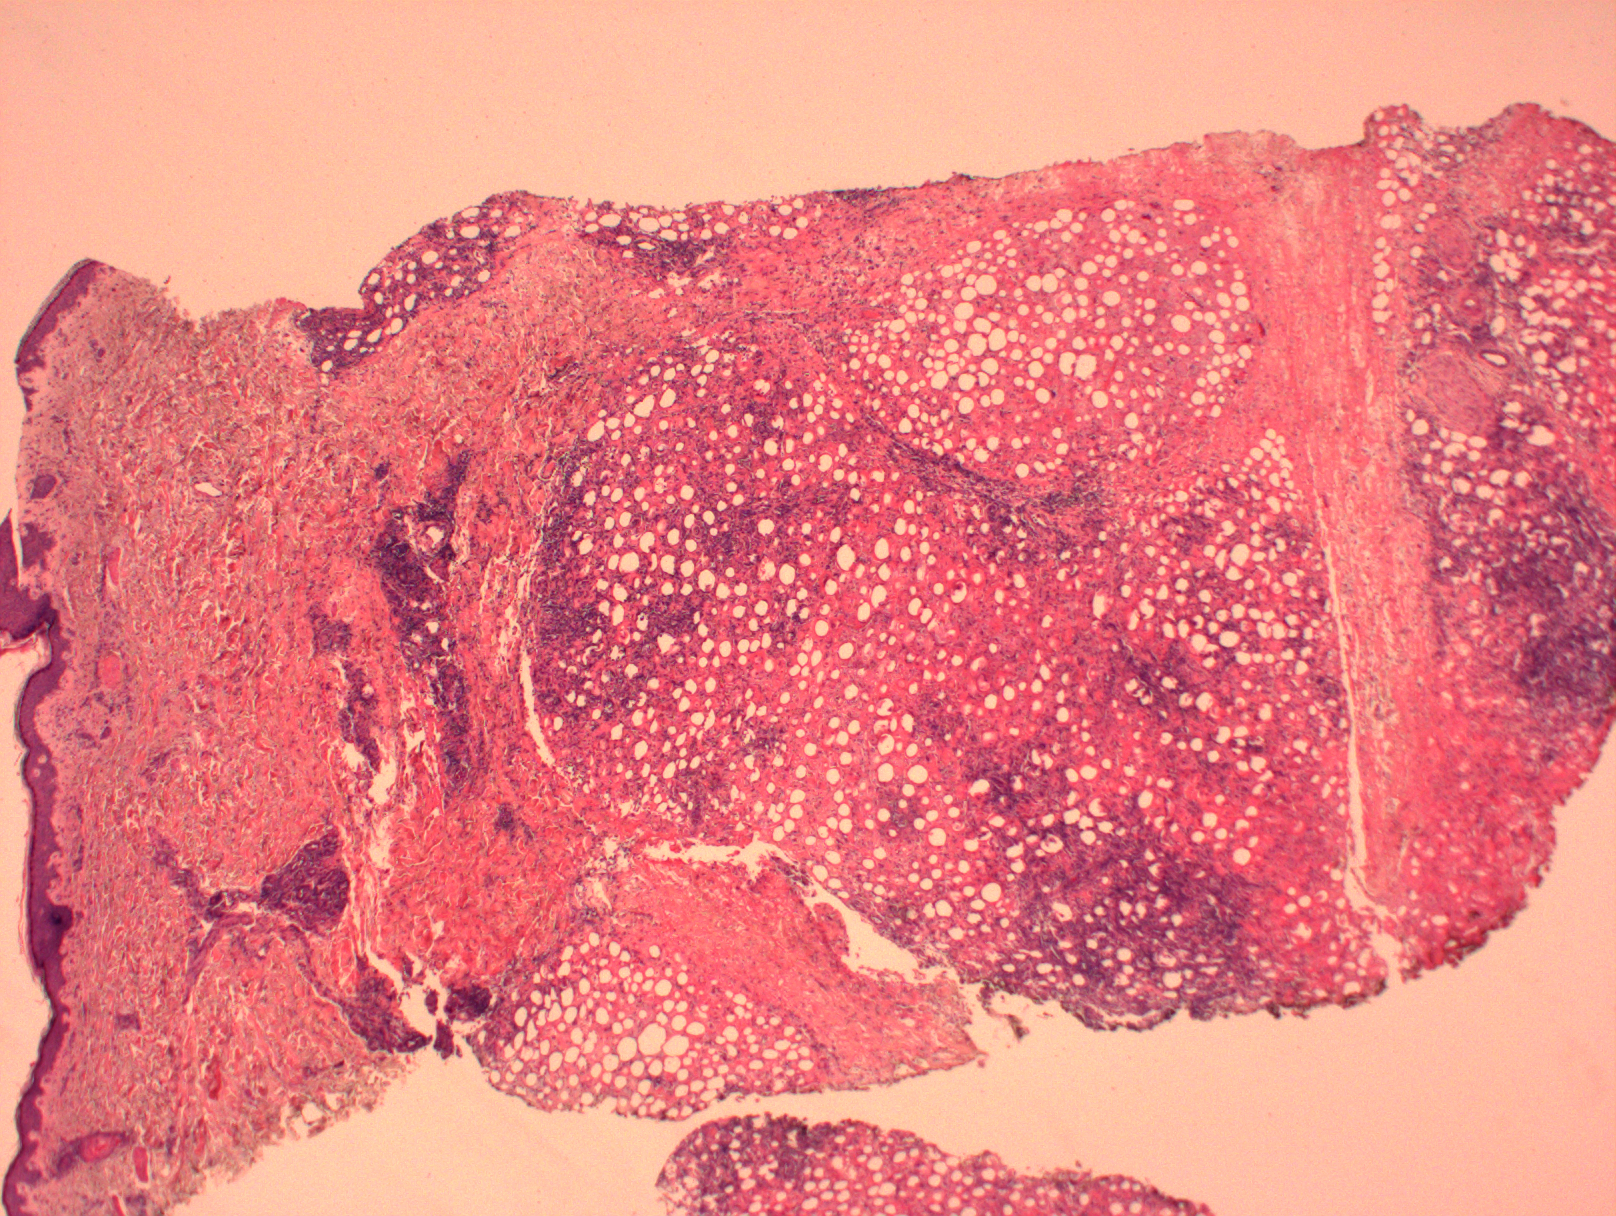

2. 肿瘤细胞主要累及皮下组织,呈现密集侵润,常见具特征性的环绕单个脂肪细胞生长。脂肪坏死常见,血管也可受累,但一般不呈现血管中心性侵润模式。